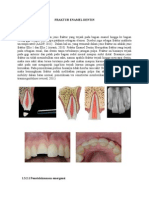

Perawatan klas I kompomer pada gigi sulung

Preparasi kavitas:

Metode preparasi kavitas klas I kompomer pada gigi sulung sebenarnya sama dengan preparasi

kavitas klas I resin komposit pada gigi sulung. 1. Tentukan outline form untuk mendapatkan retensi mekanis antara tambalan dengan gigi. 2. Dapatkan akses ke jaringan gigi yang karies menggunakan bur bulat dengan kecepatan rendah. Tidak perlu melakukan preparasi bentuk box dengan sudut-sudut yang tajam (sharp internal line angles) seperti pada preparasi amalgam. 3. Kavitas diperdalam dengan memasukkan bur perlahan-lahan sehingga kedalaman kavitas yang tercapai sekitar 0,5 1 mm. 4. Kavitas diperluas dengan menggunakan bur silindris.

Pengisian/penumpatan kompomer:

1. Setelah selesai dipreparasi, bersihkan permukaan gigi dengan pumice dan air untuk meningkatkan adhesi, kemudian keringkan sampai lembab, jangan overdrying. 2. Aplikasikan liner yang sesuai sebagai basis untuk menggantikan dentin apabila preparasi yang dilakukan mencapai dentin yang dalam. Liner yang digunakan bisa berupa resinmodified glass ionomer. 3. Aplikasikan self-etching resin bonding system (seperti Prompt L-Pop, 3M ESPE, St. Paul, Minn) untuk melekatkan compomer pada enamel gigi dan liner.

4. Bahan kompomer yang sudah tersedia dalam bentuk pasta injeksi disemprotkan/diinjeksikan ke dalam kavitas. Pada kavitas yang besar, penambalan dilakukan selapis demi selapis 5. Pada setiap lapisan kompomer yang kita tumpatkan ke dalam kavitas, di light cure selama 30 detik. 6. Gunakan bur bulat besar dengan kecepatan rendah untuk membuang kelebihan kompomer dan untuk membentuk permukaan oklusal dari gigi yang dipreparasi. 7. Lakukan pemeriksaan oklusi sentrik maupun dinamis dengan menggunakan kertas artikulasi. 8. Polishing pada tumpatan kompomer dapat dilakukan dengan menggunakan white stone, lanjutkan dengan menggunakan metal strips atau linen strips (biasa untuk tumpatan klas II dan IV), kemudian terakhir menggunakan brush yang halus. 9. Terakhir, boleh aplikasikan fissure sealant untuk melindungi permukaan oklusal yang mudah karies (mencegah terjadinya karies sekunder akibat microleakage).